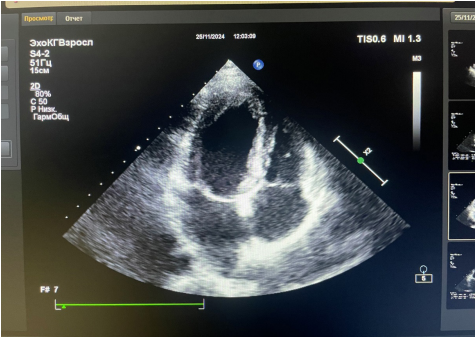

Рис. 3. Фото трансторакальной ЭхоКГ от 25.11.2024. Апикальная позиция.

Амбулаторное обращение. Жалоб нет. АД 105/60 мм рт.ст. ЧСС 80 уд./мин. ЭхоКГ: разрастание эндокарда верхушки и передне-боковой стенки ЛЖ с распространением на заднюю створку МК. Рестрикция задней стенки МК. НМК 3 ст., НТК 2 ст. Расширение ЛП. ФВ ЛЖ 53%. СДЛА 38 мм рт.ст. (рис. 3, 4). Поддерживающая терапия: метилпреднизолон 4 мг 3 таблетки в сут. |